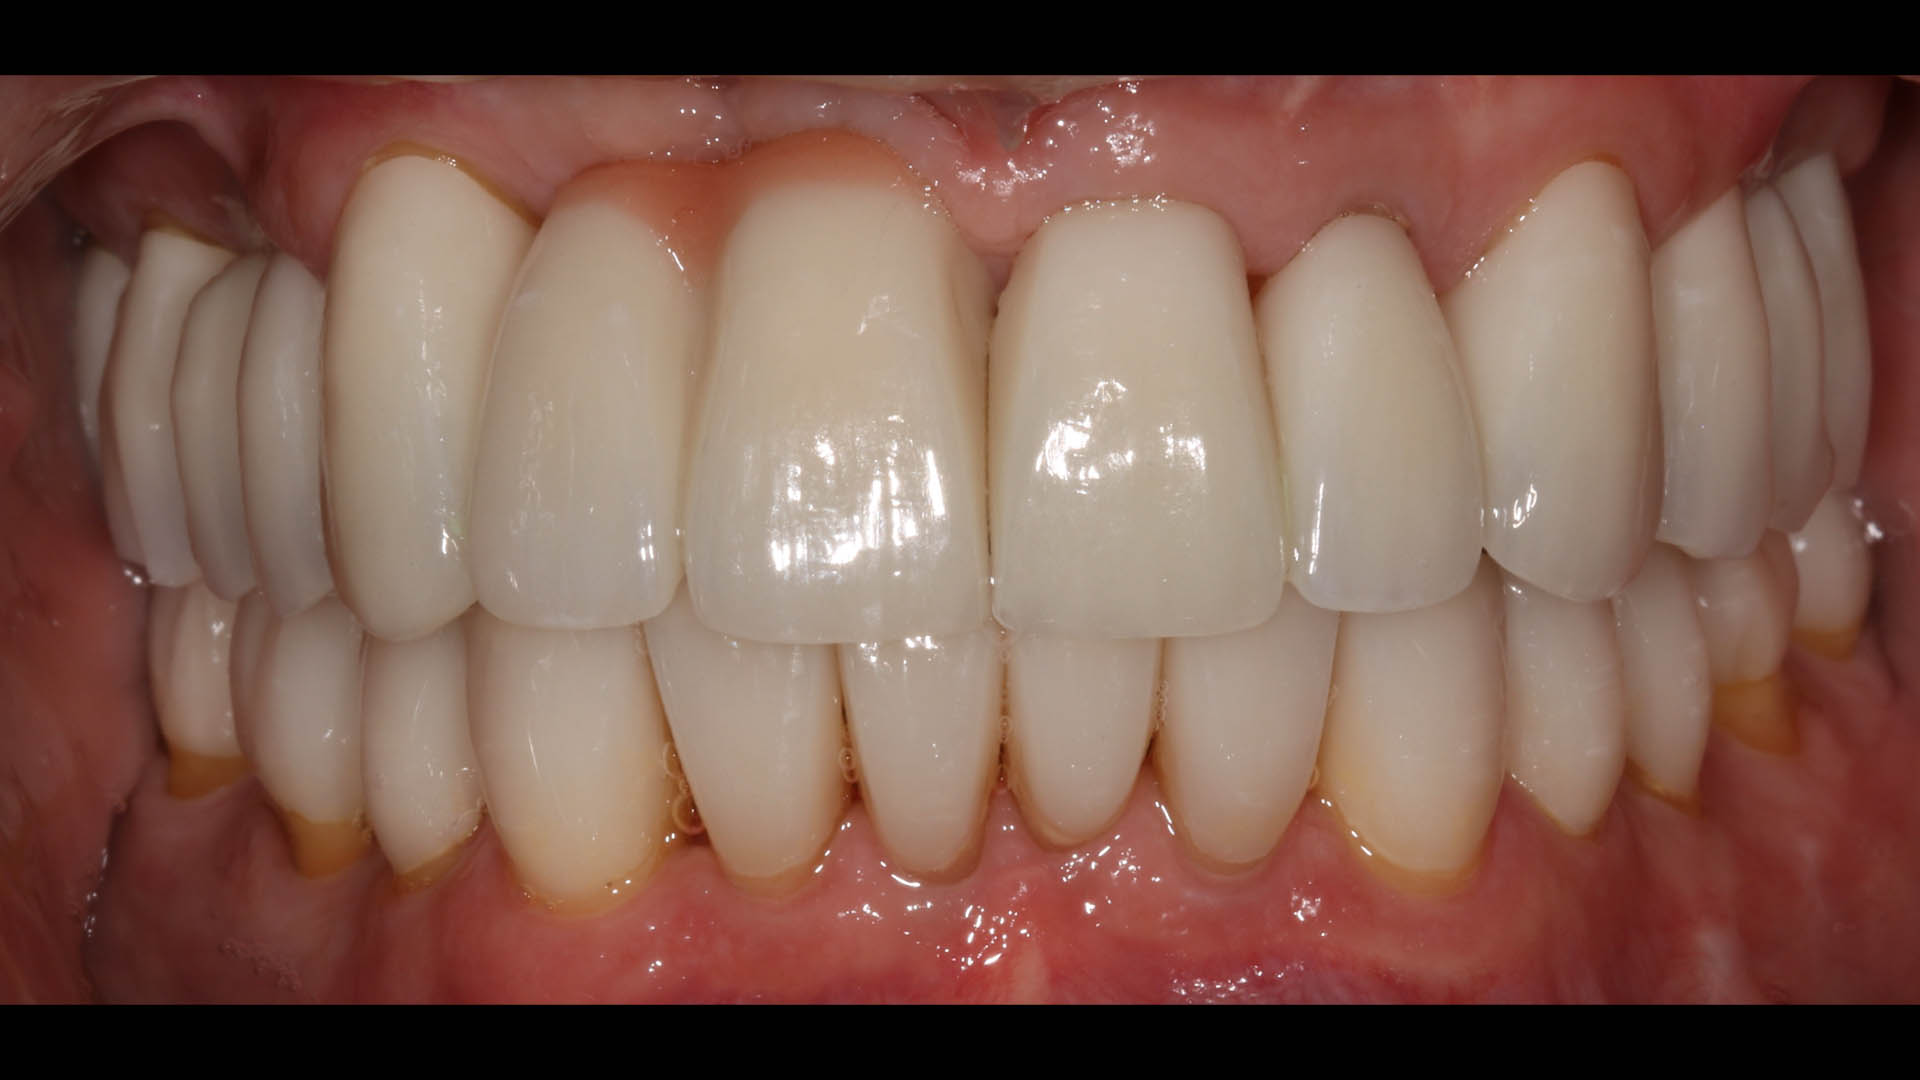

Take a glimpse into the magic of Coral Gables Dentistry through our before and after pictures. See firsthand the incredible smile makeover transformations that have brought confidence and joy to our patients.